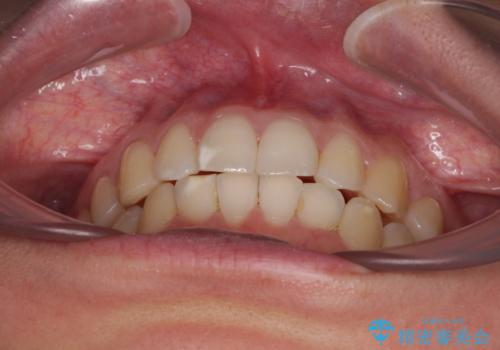

【モニター】前歯のデコボコとクロスバイト インビザラインによる矯正治療

- 上下のクロスバイトと前歯のデコボコを気にして来院された患者様です。

インビザラインを用い、IPR(歯と歯の間を削る)と歯列全体を拡大させることで、歯並びを整えていくこととしました。

下の歯が隠れてしまうほどでしたが、深い咬み合わせも改善され、顎への負担も軽減されました。